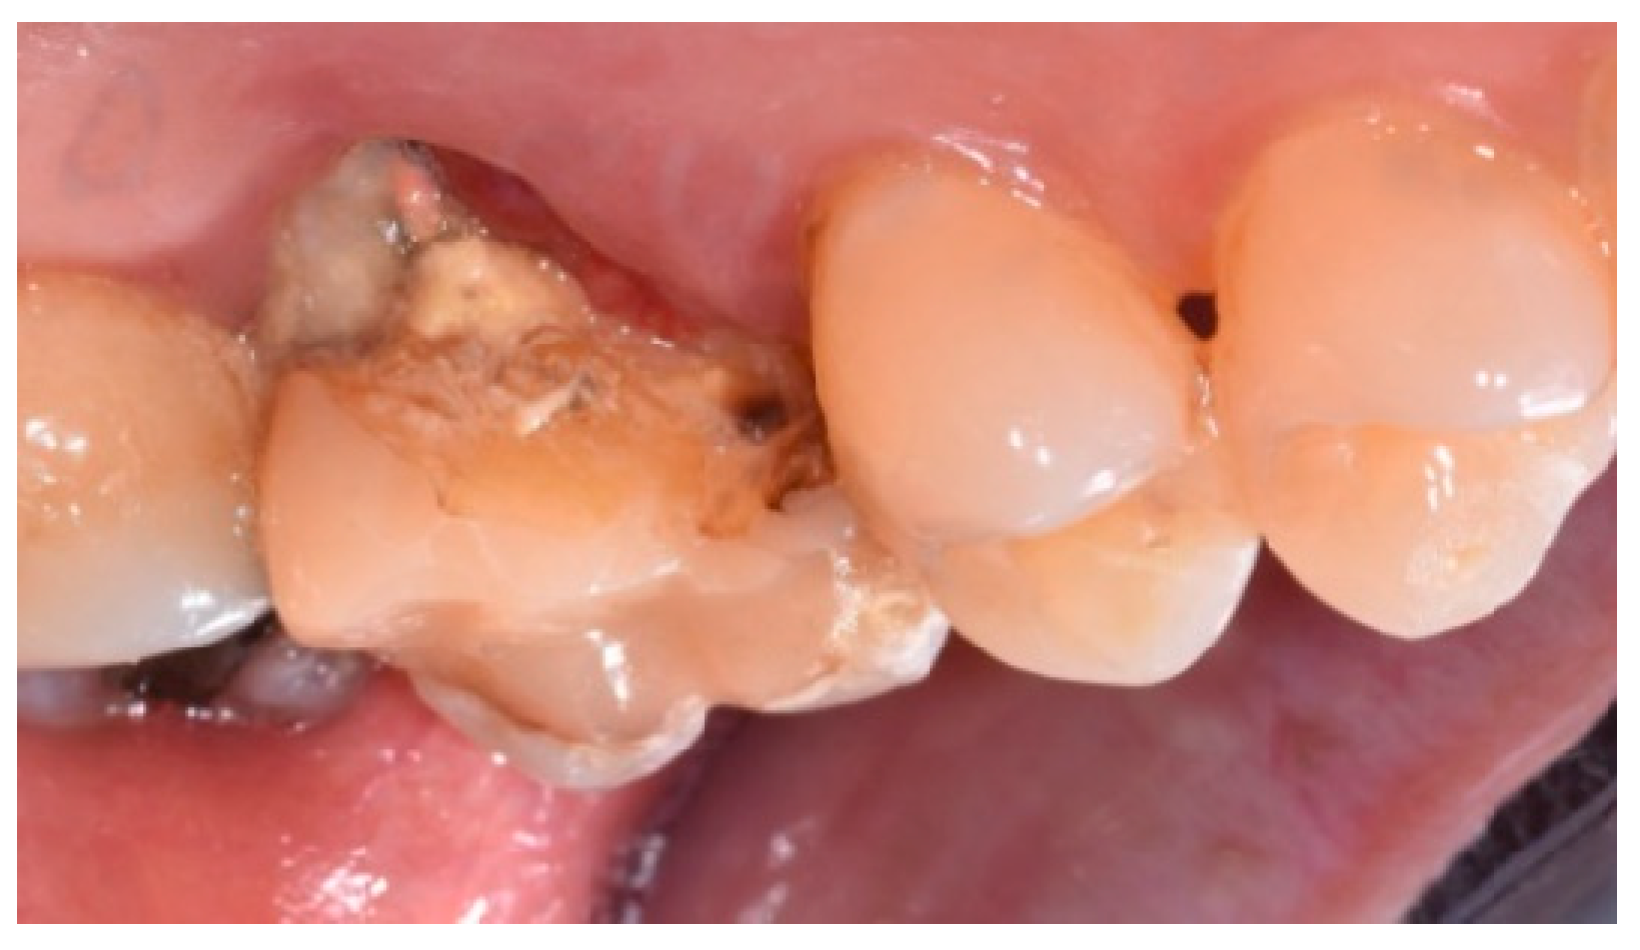

- Cause of extraction: caries, orthodontic reasons, or trauma;

- Degree of mobility (0, 1) at the time of extraction;